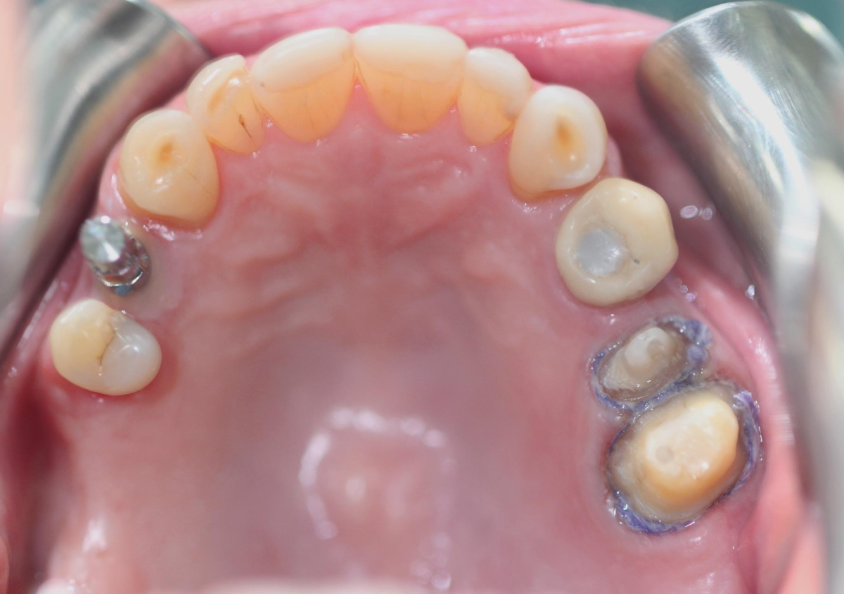

Prepare the teeth (25 and 26). The component (transfer impression) retained on the implant (tooth 14).

Take the impression and get accurate impression results with PERFIT Putty and Light Body.

Note the fluidity of the material in the gingival sulcus after gingival displacement with a retraction cord, achieving an excellent replica of the entire dental perimeter.